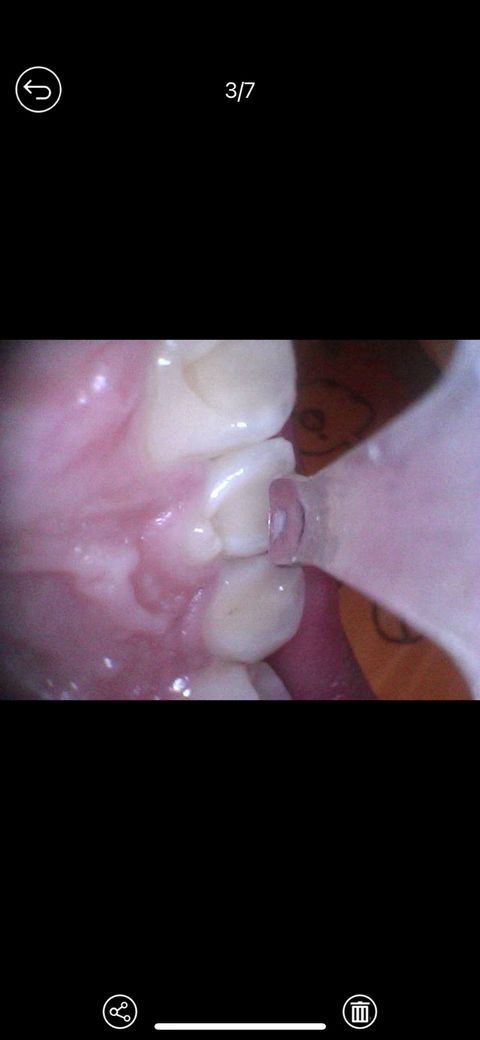

앞니 뒤에 작은이빨? 잇몸퇴축인가요??

귀파다가 궁금해져서봤는데 뭔지 모르겠어요ㅠㅠ 잇몸퇴축인건가요 아직 고등학생인데.. 아니면 작은치아가 숨어있는건가요 뭔지아시는분 답변부탁드립니다..

치아 안쪽면에 홈이 형성된 치내치로 보여집니다. 치과에 내원하여 확인하면 좋을것 같습니다. 건강하세요.

선천적으로 치아안에 치아의 구조가 하나 더 있는 듯하게 생긴 치아로 맹출하는 치내치라는 것입니다. 엄밀히 따지면 기형이기는 하지만, 다른 분들에게서도 그리 드물지만은 않게 종종 보입니다. 거울로 보이지 않는 부분이라 스스로 모를 뿐입니다. 치내치는 본치아와 튀어나온 치아사이 홈에 충치가 생기기 쉽고, 일반치아들과 내부구조도 달라서 충치가 조금만 진행돼도 신경치료를 해야할 가능성이 높습니다. 그래서 그 홈부분을 미리 메꿔서 매끈하게 만드는 예방치료를 해주시는게 좋고, 양치를 할 때 조금 더 신경써서 해주시면 좋습니다.

과잉치가 있는 것 같습니다 치과가서 엑스레이 찍어보고 위치 상태에 따라 발치가 필요할 수 있습니다